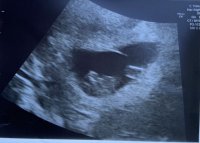

Hva tror dere? Innvendig uke 6+0